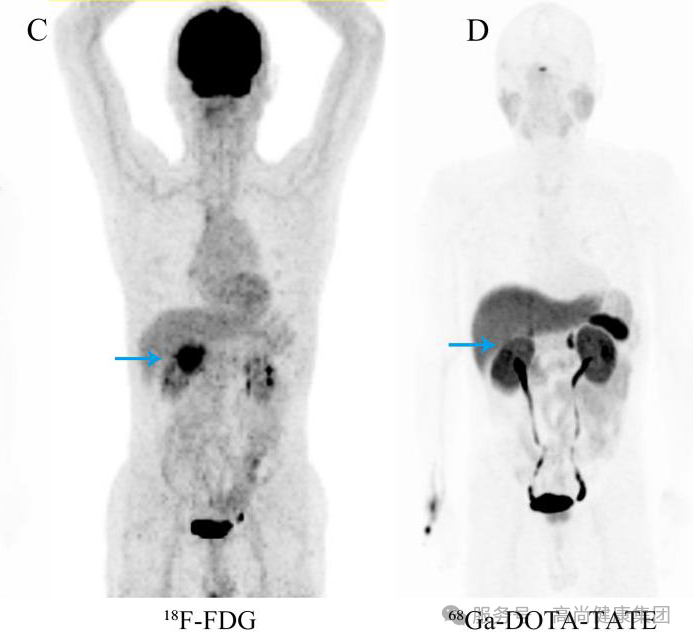

18F-FDG PET(图 C)示胃窦-十二指肠区软组织团块,代谢异常增高;

68 Ga-DOTA-TATE PET(图 D)示上述病灶为阴性,提示生长抑素受体表达水平较低。符合高级别神经内分泌肿瘤征象。[2]